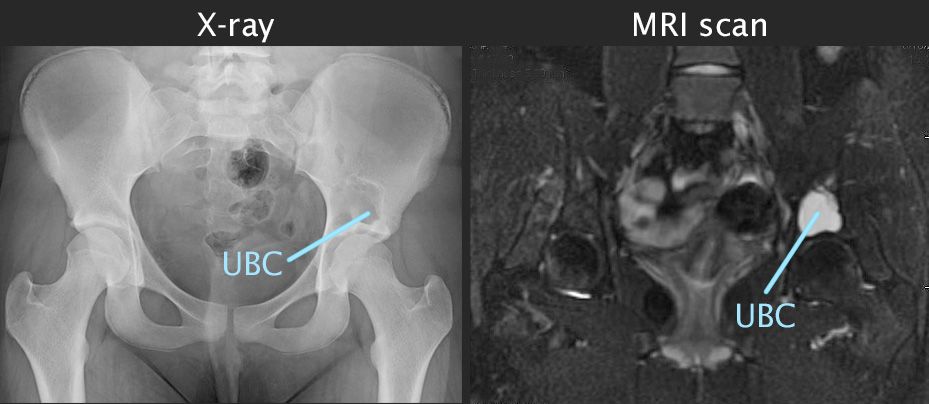

X-ray and MRI scan of unicameral bone cyst

A unicameral bone cyst in the pelvis shows up clearly in the X-ray on the left, and in the MRI scan on the right.